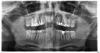

Luka Опубликовано 14 апреля, 2010 Поделиться Опубликовано 14 апреля, 2010 Специалисты помогите чайнику, Ситуация следующая ходил к ЛОР врачу лечил нос и горло, сильный отек. После долгих скитаний и обследований выяснил, что у меня большая киста в над 4 верхним слева зубом. Сходил в ближайшую частную клинику попросил открыть зуб. Стало сразу намного легче. Но проблему нужно решать и достаточно оперативно. Скорее всего придется удалять зуб, но мнения разделились. Хирург предлагает резекцию и попытаться спасти зуб с последующей установкой коронки на спасенный и соседний зуб.Ортопед предлагает удалять и ставить имплант.Понимаю, что скорее всего ортопед прав.Вопросы:1) Как лучше поступить, удалить и ждать 6 месяцев когда все заживет или сразу вставить имплант в лунку????? 2) какой имплант выбрать с точки зрения оптимального цена качество (желательно, чтобы хватило на долго)??? Снимок ниже Ссылка на комментарий